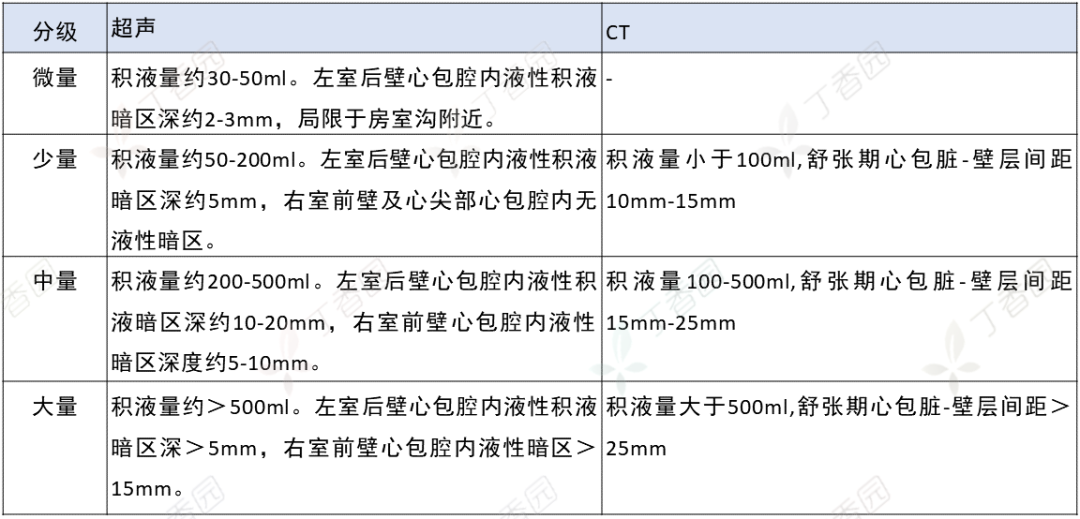

恶性心包积液( malignant pericardial effusions,MPCE) 是恶性肿瘤患者常见严重并发症之一, 原发于心包的恶性肿瘤非常少见,更多...